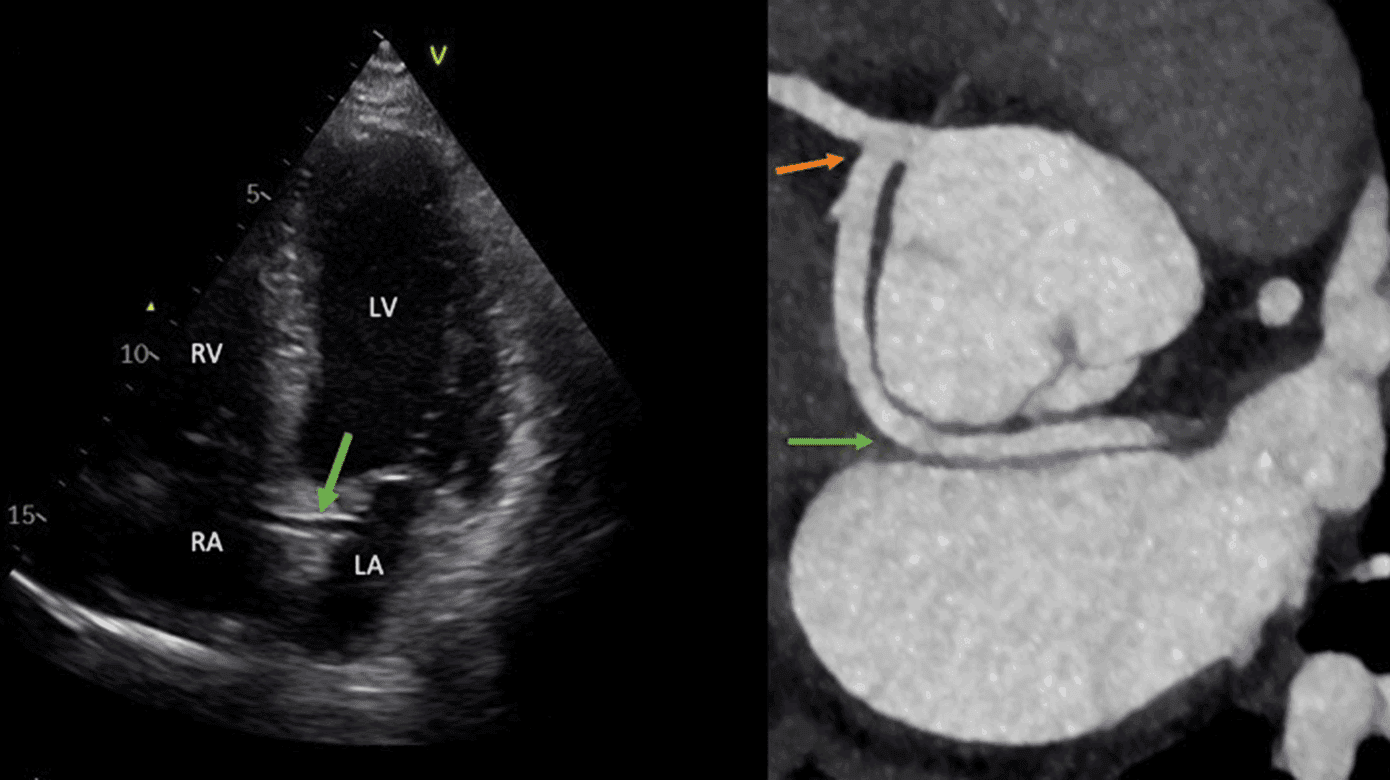

Ved indlæggelsen fandt man normale vitalværdier fraset et forhøjet blodtryk på 161/101 mmHg. Biokemien, inklusive troponinniveau, var upåfaldende. Røntgen af thorax var normalt. Et 12-aflednings-ekg viste sinusrytme med en frekvens på 84 bpm, normal overledning og ingen tegn på belastning eller iskæmi. En transtorakal ekkokardiografi var overvejende upåfaldende med normal biventrikulær systolisk funktion og uden valvulopati, pulmonal hypertension, aortopati eller perikardieekssudat. Fra flere projektioner bemærkedes et karspor foreneligt med retroaortisk anomalt koronart (RAC) tegn, hvilket rejste mistanke om koronaranomali (Figur 1A).

Hjerte-CT’en viste koronaranomali i form af ramus circumflexus (Cx) udgående fra højre koronararterie uden interarterielt forløb (Figur 1B). Der blev ikke fundet nogen stenoser, og calciumscoren var 0. Patientens symptomer blev tilskrevet supraventrikulære ekstrasystoler samt stress, og han startede i et behandlingsforløb for stress via sin egen læge med symptomatisk bedring.